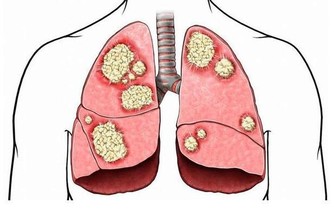

糖尿病是一種可以遺傳的代謝型疾病,如果子女遺傳了父母糖尿病發病相關的「壞基因」,子女也容易患糖尿病。實際上,就算遺傳了上一代人的糖尿病基因,子女也並非一定會得糖尿病,怎樣可以降低遺傳性糖尿病的發病風險呢最新的一項研究發現,長期堅持有氧運動,可以抑制遺傳的「壞基因」,降低糖尿病的發病機會。有氧運動,克抑制遺傳的壞基因醫學研究者欣喜的發現:堅持6個月的有氧運動,可以改善被測試者的脂肪分布方式、胰島素分泌能力和糖代謝能力,從某種程度上說:通過科學有效的鍛煉,能夠糾正與糖尿病發病有關的壞基因,減少患二型糖尿病的風險。

運動可以節約胰島素對於已經患有糖尿病的患者,積極的體育鍛煉可以幫助降血糖。

眾多的測試和研究結果證明:當人體在運動的時候,肌肉就會收縮,細胞膜會打開一些通道,血糖更容易進入細胞裡,為細胞供能。

也就是說,運動可以節約胰島素,身體不需要分泌那麼多的胰島素,血糖就能更容易的進入細胞,這樣一來,就能起到降血糖的效果。

糖友運動,量力而為如果身體條件允許,持續的中強度運動,可以讓血糖進入肌肉細胞的速度增加20倍,比降糖藥的效果還要好!